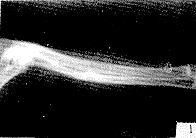

图1 实验组兔 第2周末X线片示骨折断端有明显骨痂形成,骨折线较模糊

图2 对照组兔 第2周末X线片示骨折断端少许骨痂,骨折线清晰

图3 实验组兔 第8周末X线片示骨折线完全消失,髓腔通畅

图4 对照组兔第8周末X线片示骨折线基本消失,骨痂密度较高,髓腔未通

Fig. 1 X-ray of the fracture site in the experimental group by the end of the 2nd weekend: Lots of callus at the fracture site, the unclear fracture line

Fig. 2 X-ray of the fracture site in the control group by the end of the 2nd weekend: A little callus, clear fracture line

, 百拇医药

Fig. 3 X-ray of the fracture site in the experimental group by the end of the 8th weekend: Disappeared fracture line unimpeded pulp cavity

Fig. 4 X-ray of the fracture site in the control group by the end of the 8th weekend: Nearly disappeared fracture line, the high density callus and impeded pulp cavity

2.1 骨折愈合状况 实验组动物94%(15/16)在第2周末即有明显骨痂形成(愈合Ⅱ级),第6周末骨折线已基本消失,8周末全部骨折部位已基本塑型完毕,完全愈合(愈合Ⅴ级);对照组第2周末尚未见明显骨痂,4周末有骨痂形成,8周末骨折线才趋于消失,但尚未见骨痂塑形,髓腔未完全通畅。两组X线骨愈合资料见表1及图1~4。经统计学分析,两组动物不同时间差异均有显著意义(P<0.01或P<0.05)。